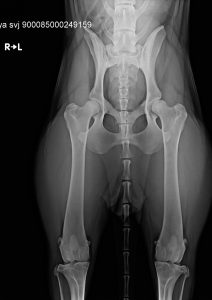

Egészségügyi szűrések